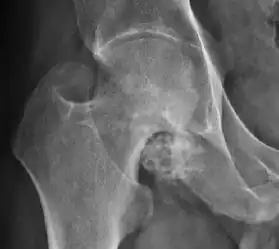

- Osteoarthritis

In adults, one of the main indications for radiographs is the detection of osteoarthritic changes (Figure 1(e)). Nevertheless, radiographs usually detect advanced osteoarthritis that can be graded according to the Tönnis classifications. The grading system ranges from 0 to 3, where 0 shows no sign of osteoarthritis. Intermediate grade 1 shows mild sclerosis of the head and acetabulum, slight joint space narrowing, and marginal osteophyte lipping. Grade 2 presents with small cysts in the femoral head or acetabulum, moderate joint space narrowing, and moderate loss of sphericity of the femoral head. Grade 3 is the severest form of osteoarthritis, which manifests as severe narrowing of the joint space, large subchondral cyst with productive bone changes that may lead to deformity of the bone components of the joint, while secondary osteoarthritis due to calcium pyrophosphate deposition can be diagnosed when calcification of hyaline cartilage and fibrocartilage is detected.[1]

There are other pathological conditions that can affect the hip joint and radiographs help to make the appropriate diagnosis. Acute bacterial septic arthritis can be diagnosed by radiographs when a fast regional osteoporosis and destructive monoarticular process develops (Figure 1(f)). In case of tuberculous or brucella arthritis it is manifested as a slow progressive process, and diagnosis may be delayed.[1]

Synovial chondromatosis can be confidently diagnosed by X-ray when calcified cartilaginous chondromas are seen. However, other synovial proliferative processes, such as pigmented villonodular synovitis, require MRI for accurate diagnosis, although noncalcified synovitis can be suspected in radiographs by indirect signs, such as soft tissue swelling and/or erosions in the femoral head, femoral neck, or acetabulum (Figure 7).[1]